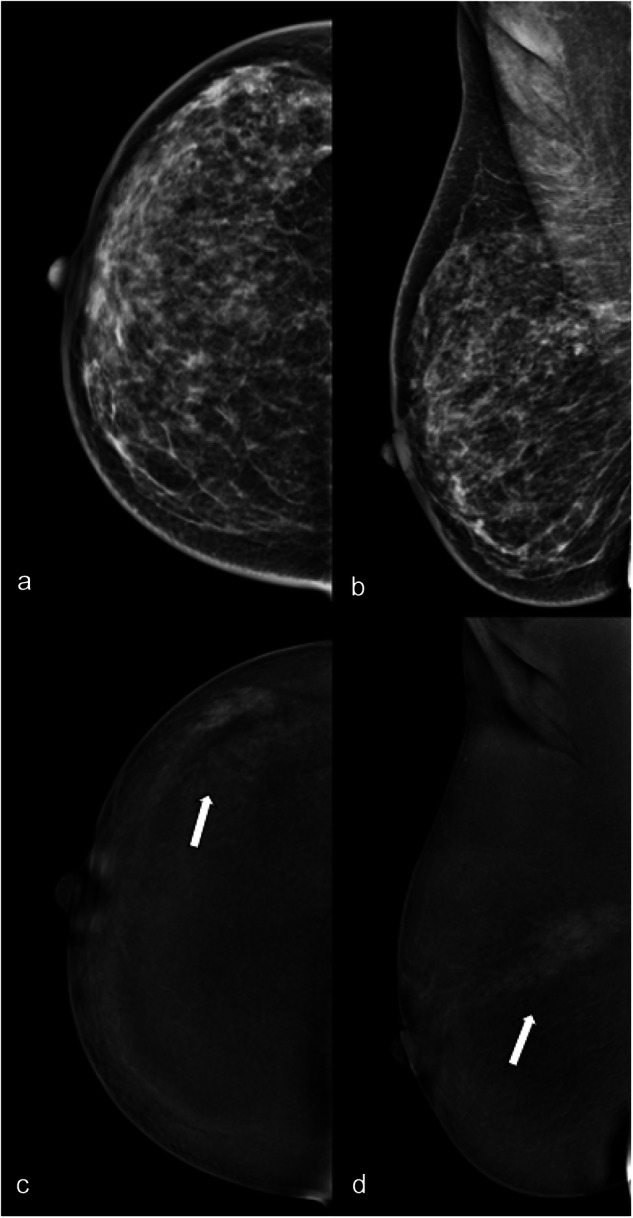

Fig. 1.

LE (a, b) and RC (c, d) CEM images of the right breast of a 32-year-old patient with nipple discharge. The three readers evaluated in separate sessions ACR density (c, unanimously); type of lesion (microcalcifications for two of the three readers, mixed for the third); presence/absence of associated architectural distortion (absence, unanimously) on LE images; type of enhancement (white arrows: non-mass, unanimously); lesion conspicuity (high, unanimously) and non-mass enhancement descriptors (non-mass distribution segmental, unanimously; and the non-mass internal pattern of enhancement heterogeneous for two of the three readers, clumped for the third) on RC images. The level of suspicion on LE was BI-RADS 4, unanimously, and on RC BI-RADS 4 for two of the three readers and 5 for the third. Histology was ductal carcinoma in situ with micro invasion

The overall agreement between the three readers was moderate for breast density and substantial for lesion type on LE images (Table 1). There was an almost perfect agreement in the identification of microcalcifications (ĸ = 0.820) (Fig. 1). The inter-reader agreement for the identification of architectural distortion was moderate (ĸ = 0.496).